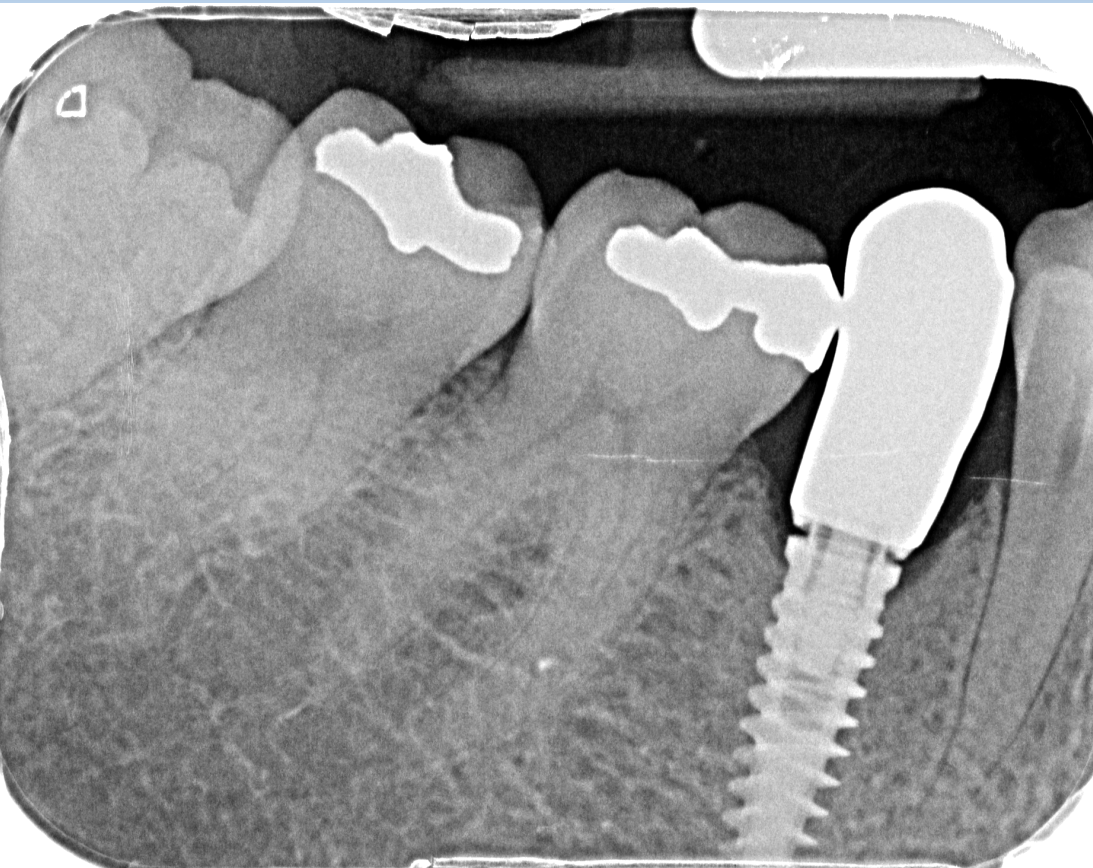

Buenos días compañer@s! Me llega a la clínica este caso... tengo que rehabilitarlo, me podríais ayudar a identificar los implantes? Muchas gracias de antemano!!!!!!!!!

De clínica nos llegan estas fotos para ver si sabemos cual es el implante que lleva la paciente. El implante se colocó en I Dental hace un año aproximadamente. Espero [...]